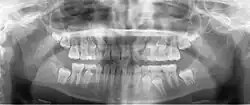

Panoramic radiograph

A dental panoramic radiograph, showing the maxilla and mandible, all the teeth including the "wisdom teeth," the frontal and maxillary sinuses, the nasal cavity and the temporomandibular joint and other near by head and neck anatomy. | |

A panoramic radiograph is a panoramic scanning dental X-ray of the upper and lower jaw. It shows a two-dimensional view of a half-circle from ear to ear. Panoramic radiography is a form of focal plane tomography; thus, images of multiple planes are taken to make up the composite panoramic image, where the maxilla and mandible are in the focal trough and the structures that are superficial and deep to the trough are blurred.